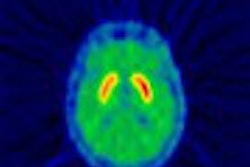

VIENNA - Fusion PET-CT scanners offer a powerful combination of functional and anatomical data that can give radiologists precise information on tumor location and stage. But MRI still has a strong role to play in oncology imaging, as both modalities demonstrate different strengths and weaknesses in tumor visualization, according to German researchers at this week's European Congress of Radiology.

A group from University Hospital in Essen presented a comparison of PET-CT and MRI in Monday's ECR scientific sessions. The group also discussed its work in using PET-CT to track radiation therapy treatment, as well as in reducing respiratory artifacts on PET-CT studies with a new breathing protocol.

In the first study, Dr. Gerald Antoch compared PET-CT to MRI in visualizing tumors in 50 patients. The group used a dual-slice biograph PET-CT scanner (Siemens Medical Solutions, Erlangen, Germany) and a 1.5-tesla Magnetom Sonata MRI unit (Siemens), equipped with a rolling table (bodySurf). The field of view was set from the head to the upper thigh, and patients received MRI scans with a gadolinium-based contrast agent.

The modalities were found to be comparable in 33 (66%) patients, and the abdominal organs were assessed equally well in all patients, Antoch said. PET-CT beat MRI in detecting lymph node and pulmonary lesions, however.

In eight patients (16%) with cervical, thoracic, or abdominal lymph node tumors, PET-CT was able to detect tumors missed on MRI due to their small size (less than 1 cm). PET-CT spotted 94 pulmonary lesions in 16 patients, compared to 58 lesions in 13 patients for MRI.

MRI excelled in visualizing bone metastases, however, finding metastases in 7 patients (14%) that were missed on PET-CT.

"Whole-body PET-CT seems to be superior to whole-body MRI in detecting lymph node metastases and pulmonary lesions," Antoch said. "On the other hand, whole-body MRI detects bone metastases more accurately. Whole-body PET-CT and MR imaging complement each other in the staging of malignant diseases."